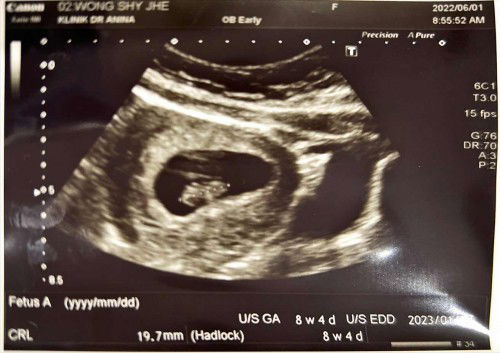

8 Weeks 4 Days

Hi, hari tu saya ada post status mengenai positif line samar2 semasa 6 hari sebelum haid. so hari ni saya pergi ke klinik untuk buat scan, finally dapat juga tengok baby dalam rahim & degupan jantung pun dah boleh dengar. sekarang 8 weeks & 4 days 🥰 next week dah dpt appointment untuk buka buku kehamilan. this is my first experience. semasa dengar degupan jantung tu, rasa mcm nak nangisss ja 🥹 sebab tak percaya sebab sya membawa 1 nyawa lagi bersama saya 😁